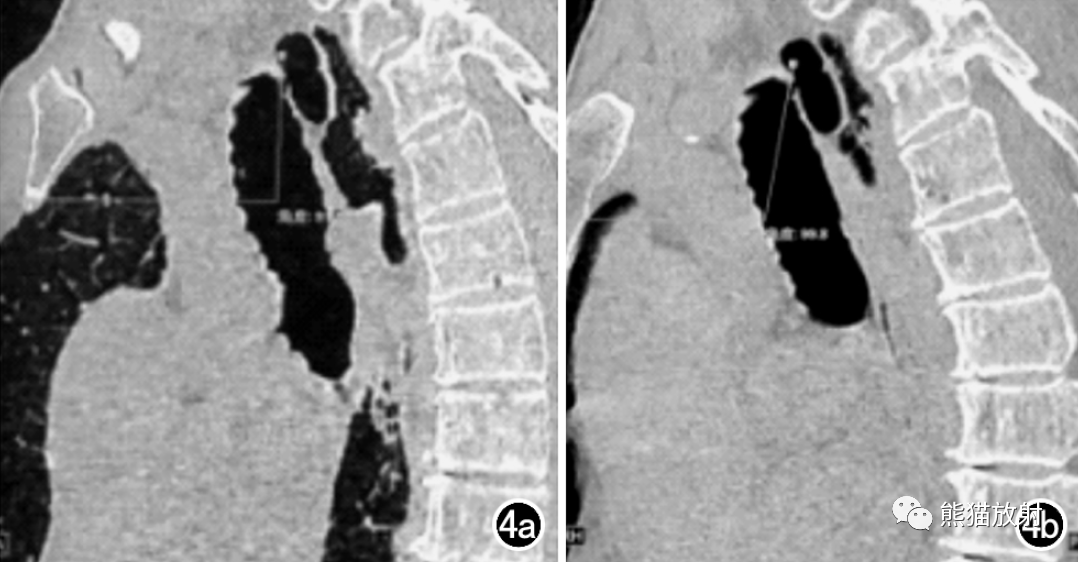

男,76岁。a)首次CT检查胸部矢状面MPR示TD充气,AFDT与水平线夹角为91.8°;b)一年半后随访复查示TD充气,AFDT与水平线夹角为99.8°。